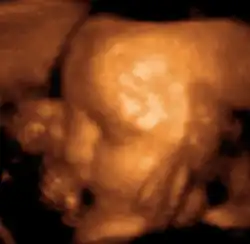

También se emplea para visualizar fetos durante la atención rutinaria prenatal y de emergencia. Dichas aplicaciones de diagnóstico utilizadas durante el embarazo se denominan ecografía obstétrica, la cual veremos a continuación.

Obstetricia

Esta técnica diagnóstica también se conoce como ecografía o sonografía.[16]

La máquina de ultrasonido tiene cristales piezoeléctricos que al ser estimulados por electricidad vibran produciendo ondas sonoras de alta frecuencia que hacen eco en las estructuras corporales retornando a los cristales que nuevamente estimulados ahora por ultrasonido producen pequeños voltajes que son procesados de acuerdo a su intensidad y tiempo de retorno mediante un computador que tiene un convertidor de barrido digital creando así las imágenes. A diferencia de los rayos X, en este examen no se presenta ninguna exposición a la radiación ionizante y no se ha detectado ningún riesgo utilizado con los aparatos apropiados para diagnóstico. En la actualidad existen ecógrafos del tamaño de un celular que pueden ser empleados para diagnóstico inmediato.[17]